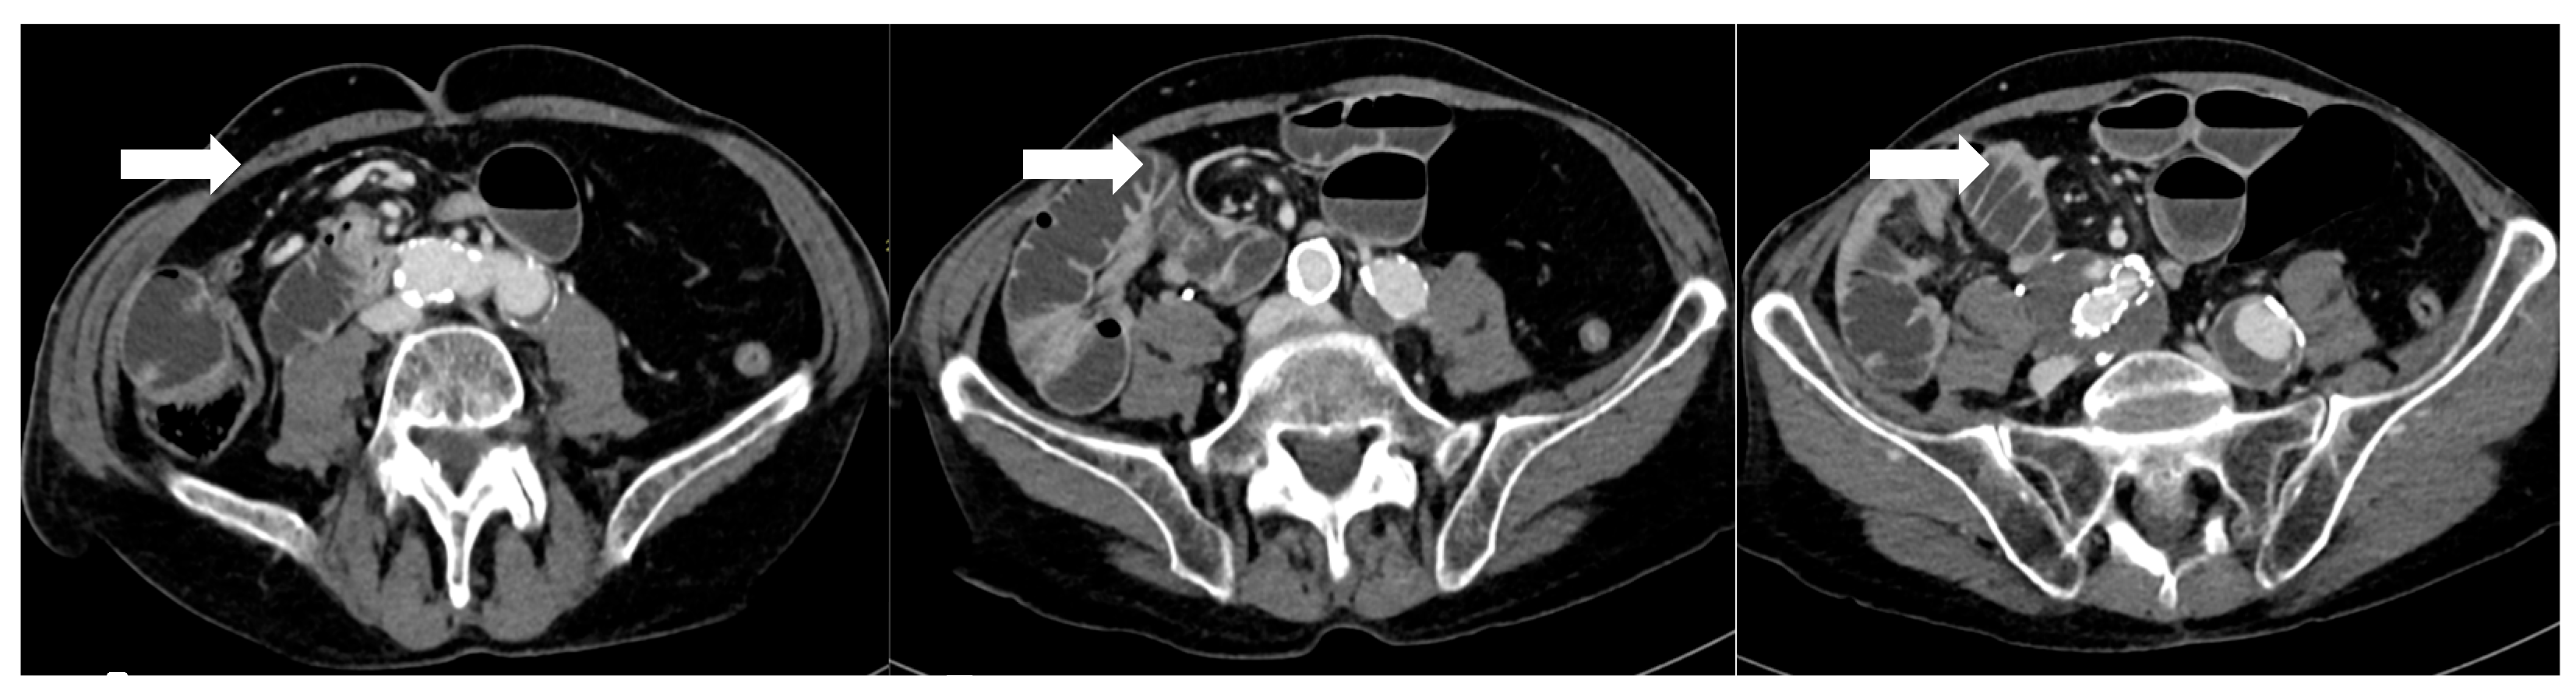

Figure 3.

After 5 days from sleeve gastrectomy, axial post-contrast CT scans showing an angulated course of the duodenojejunal junction to the right of the midline, with evidence of a mesenteric “whirlpool sign,” suggestive of intestinal malrotation (arrows). The copyright of this figure belongs to the authors.